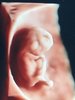

Mam na imię Natalia, mam 27 lat i właśnie spodziewam się drugiego Skarba ❤️ Jest to dla mnie dosyć szybko ponieważ w październiku 2017 urodziłam synka przez CC. Przerwa między ciążami dosyć krótka wiec jestem pełna obaw ale mam nadzieje ze wszystko będzie ok z blizna, zdrowiem a przede wszystkim maluszkiem. Mimo wszystko bardzo się cieszymy z tej ciąży, choć jest dla nas niezłym zaskoczeniem ale o synka staraliśmy się 1,5 roku z różnymi przebojami. Wiec fakt zajścia w ciąże tak poprostu to dla nas duży cud. Termin z miesiączki mam na 25 marzec. Dziś właśnie skończyłam 11 tydzień :) w tej ciąży okazało się ze mam nieduża niedoczynnosc tarczycy i biorę Euthyrox, nigdy wcześniej nie miałam problemów z tarczyca.

Mam tez co jakis czas plamienia (biorę spore dawki magnezu i duphaston- ta sama przypadłość w pierwszej ciąży), ale obrazowo wszystko z dzidzia ok :) taki mój urok podobno...

Wstawiam zdjęcie dzidziusia z ostatniej wizyty, mam nowa gin która ma super sprzęt :)

CB571CEC-EB41-4AC1-8CE4-E845F41A36F5.jpeg

573 KB · Wyświetleń: 335